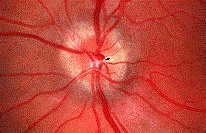

问题 视盘水肿与视盘炎(如图)的鉴别主要依据是 ( )

选项 A、视盘水肿时视盘高起多超过3D B、视盘水肿是色淡 C、视盘炎开始时视力明显下降 D、视盘炎时生理盲点扩大 E、视盘水肿开始时视力减退明显

答案 AC